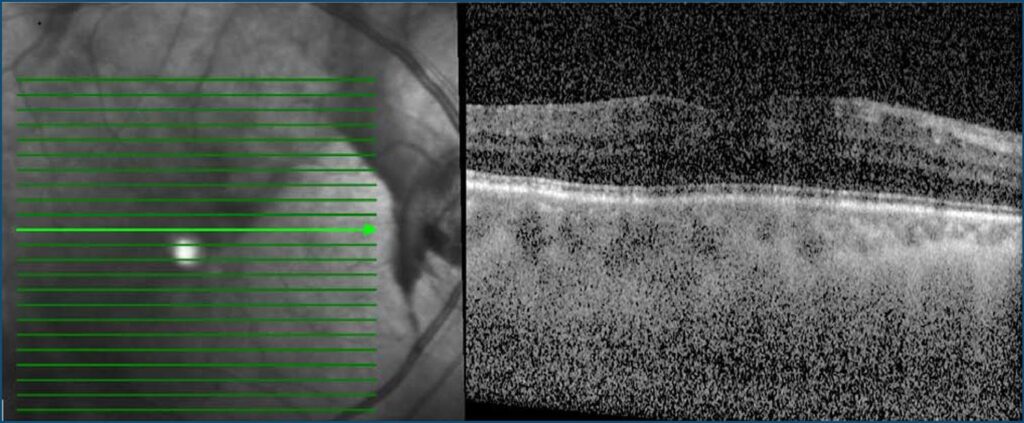

A 10-year-old Malay girl with underlying HbE/beta-thalassemia, on regular blood transfusion and deferoxamine iron chelation therapy, presented with two-month history of bilateral blurring of vision. On examination, her vision was 6/36 both eyes. Other optic nerve functions were normal. Anterior segment examination of both eyes was unremarkable. Fundus examination of both eyes revealed dull foveal reflex. Optical coherence tomography of both maculae showed increased central subfield thickness. Fundus fluorescence angiography showed patchy hypofluorescence over macular region for both eyes and late staining, indicating retinal pigment epithelium anomalies. A diagnosis of iron-chelation-therapy-related bilateral maculopathy was made. Patient was co-managed with pediatric hematology team to adjust the dose of deferoxamine, and was given three monthly appointments to monitor the progression of maculopathy at the ophthalmology clinic. However patient defaulted ophthalmology follow-up after the first visit.